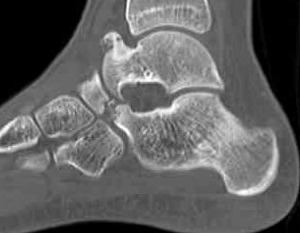

CT

TC coalition middle facet

Complete synostosis of the medial TC joint with OA of the posterior subtalar joint